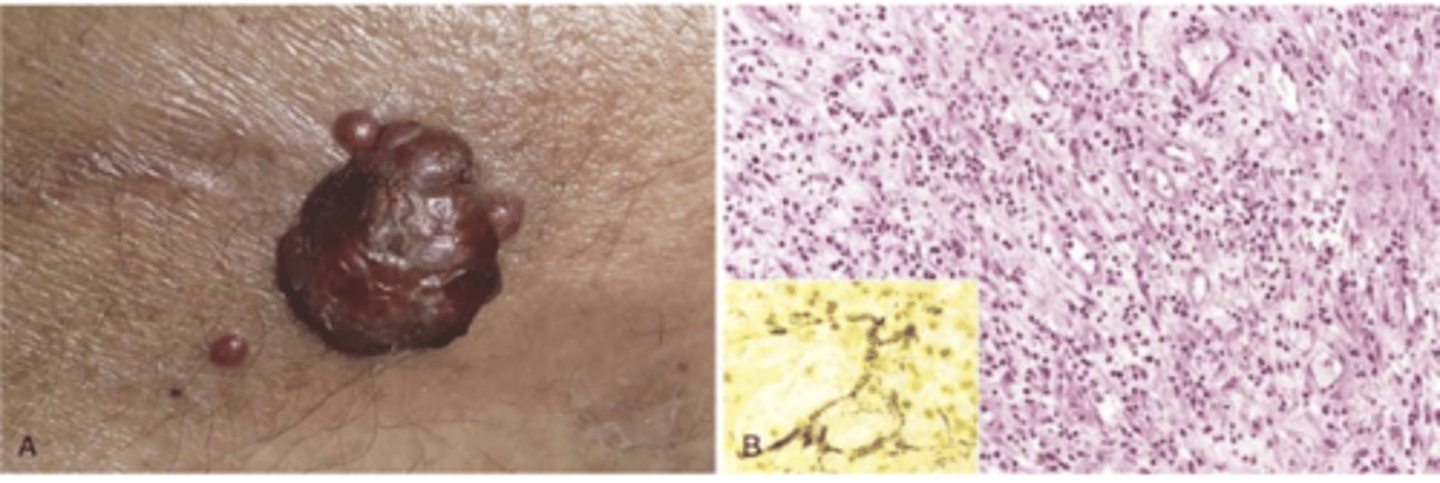

bacillary angiomatosis

vascular proliferation in immunocompromised hosts caused by bartonella infection

driven by VEGF production

treatment for bacillary angiomatosis